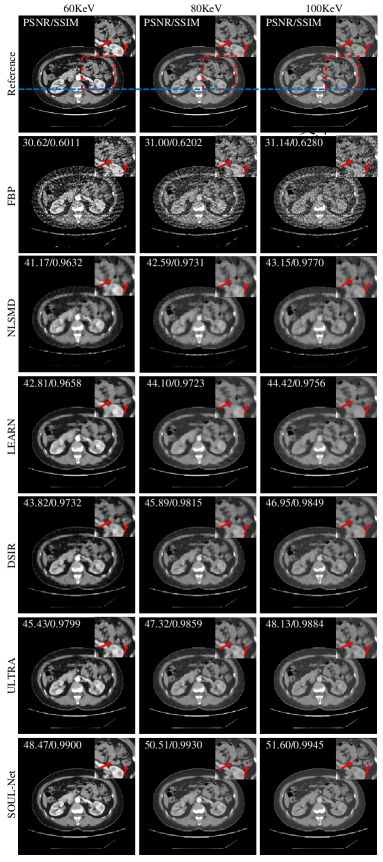

Fig. 2 shows one representative abdominal slice reconstructed with simulated noisy data using different methods. Three typical energy bins (60 keV, 80 keV and 100 keV) are displayed. It can be seen that some details in the NLSMD result are blurred, although most noise and artifacts are suppressed. Similarly, some important structural details are smoothed by LEARN, DSIR and ULTRA. To better visualize the performance of detail recovery, the ROI indicated with red boxes in Fig. 2 are magnified. It can be observed that compared with other methods, SOUL-Net not only eliminates the noise and artifacts effectively but also maintains the structures effectively, especially in the parts indicated by red arrows. The SSIM and PSNR values of each reconstruction are shown in the upper left part of each subfigure in Fig. 2. Our method achieves the highest SSIM and PSNR values.

To better verify the detail recovery ability, Fig. 3 shows the absolute difference images associated with the reference image. In Fig. 3, it is clear that SOUL-Net has the smallest residual compared with other methods. This indicates that our method is able to preserve the structural details effectively.